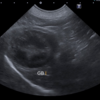

レントゲン検査、超音波検査にて腸管内に閉塞所見が認められました。